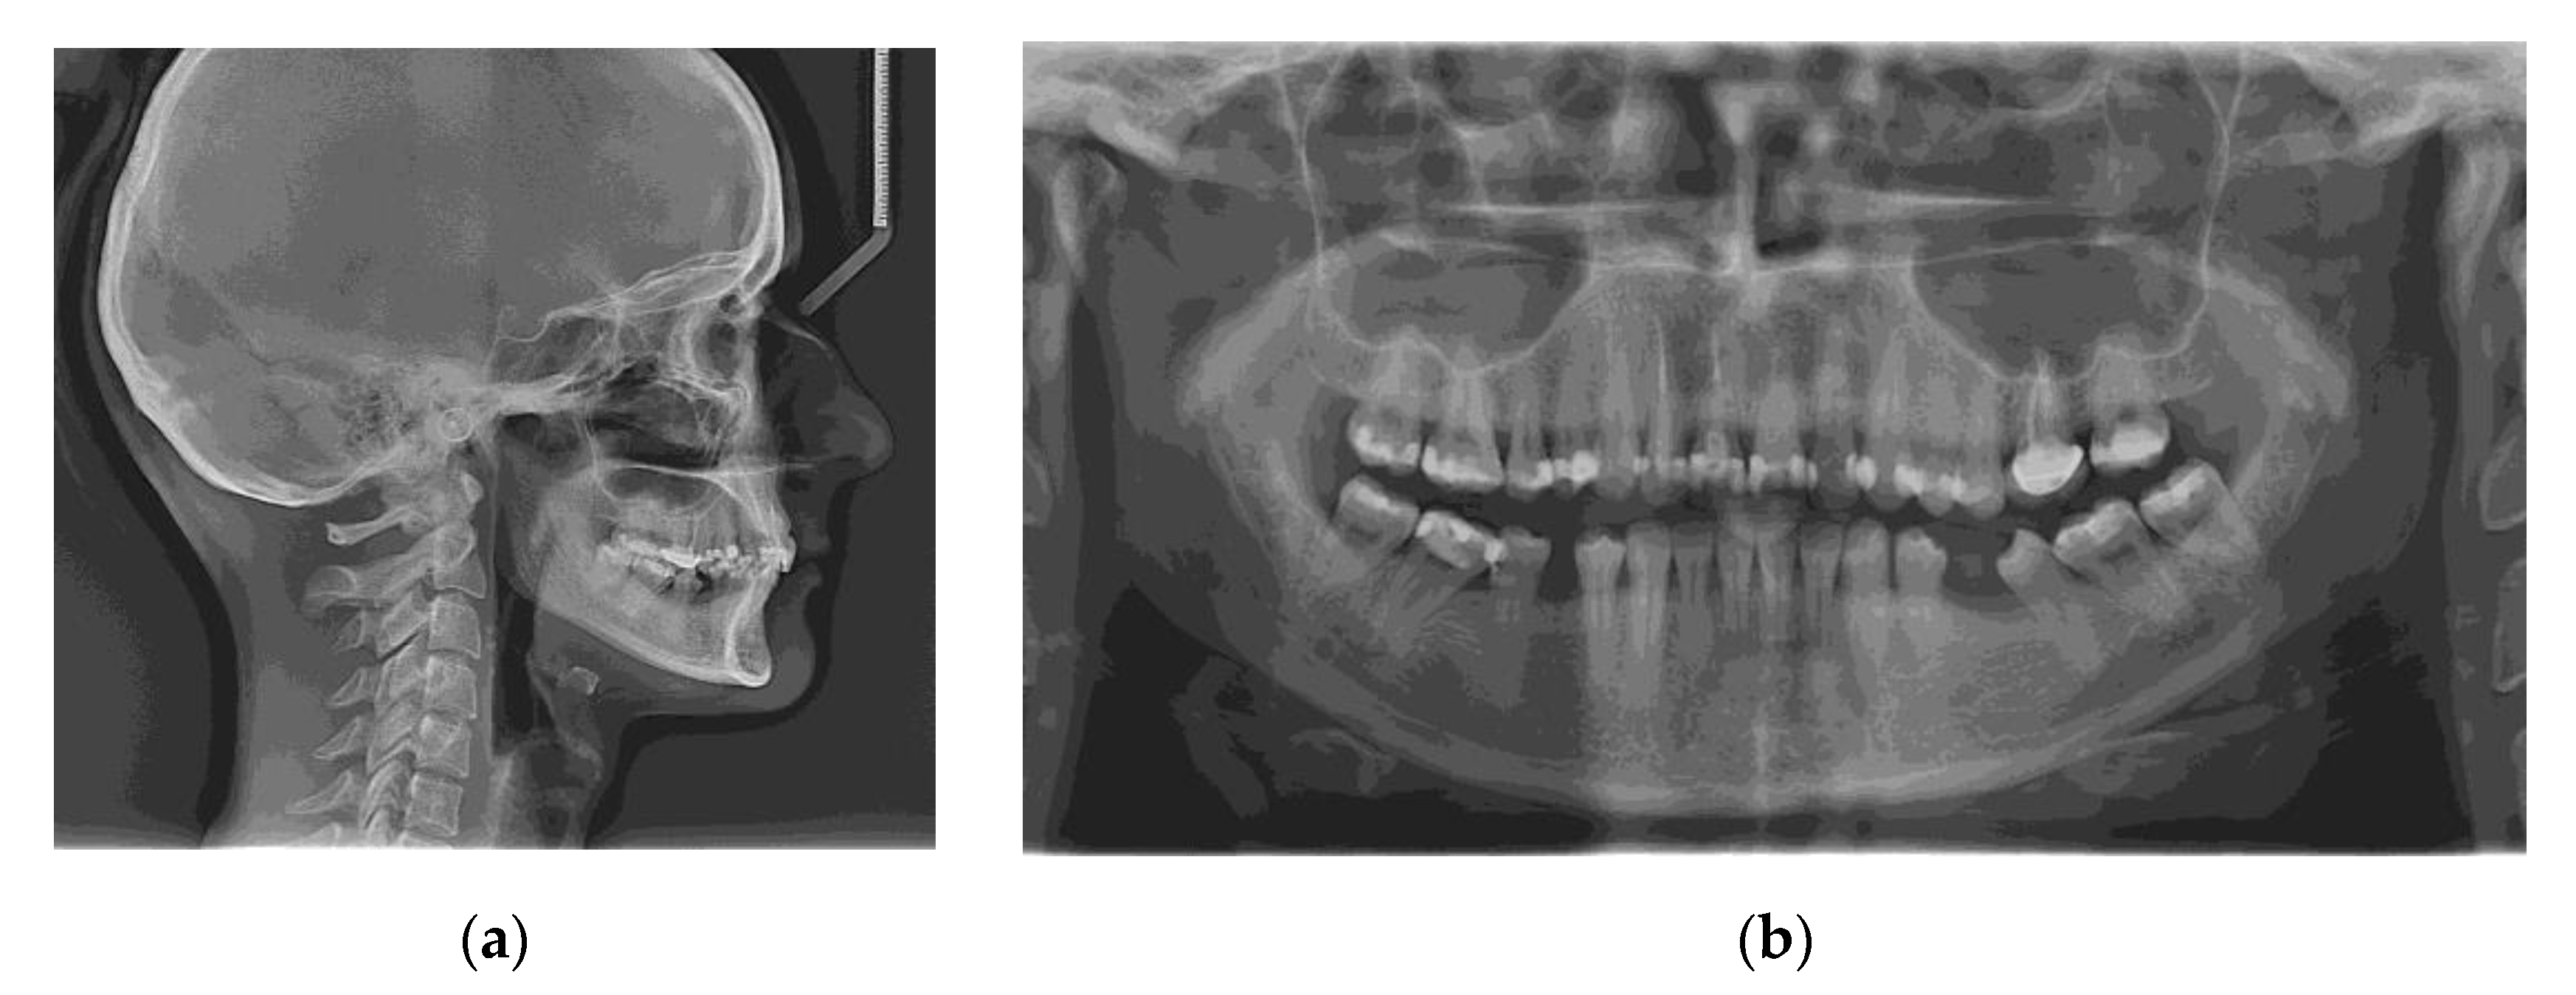

The initial radiographs are shown in Figure 3. No signs of periodontal disease or other associated pathologies were encountered on panoramic radiography.

Figure 3.

Radiographic examination before treatment: (a) Initial lateral cephalogram; (b) Initial panoramic radiograph.